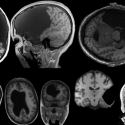

A Wearable Brain-Stimulation Device

03/22/21 Designing a wearable device to study brain function and dysfunction, with a goal of precise therapeutic interventions to treat neurodegenerative diseases Shawn Kelly

Cracking the Neural Code for Speech

01/27/12 vThe Neural Prosthesis Lab at Boston University demonstrates the Brain-Computer-Interface: a communication device for the severely impaired. Frank Guenther

Neural Disruption and Motor Dysfunctions

12/10/20 How neuroscientists probe the neural mechanisms behind disorders such as Parkinson's disease and other motor dysfunctions.. Jill Crittenden.

New Ways of Imaging the Brain

08/16/18 A visit to the Alan Jasanoff Lab at MIT to learn how brain scientists are developing new techniques and devices to improve brain imaging.

Revealing the Brain through States of Unconsciousness

11/15/11 Important insights into the brain from research on anesthesia, coma and sleep. Emery N. Brown